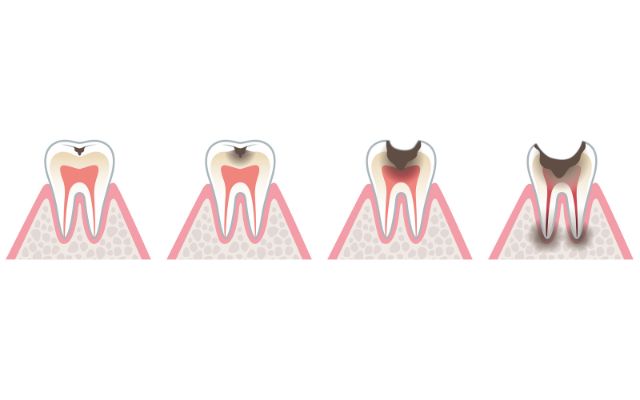

むし歯の進行度について

むし歯は進行度合いで「CO」から「C4」に分類されます。

・歯の表面の白い斑点ができる(CO)

歯の表面のエナメル質が酸性になると、エナメル質のカルシウム成分が少なくなる「脱灰」という現象が進み、歯の表面に「ホワイトスポット」と呼ばれる白い斑点ができます。この段階であれば、ブラッシングやフッ素塗布だけで改善することが可能です。

・歯に穴があく、黒ずむ(C1)

「ホワイトスポット」の状態からむし歯が進行すると、歯の表面のエナメル質がさらに溶かされて黒ずんできます。この段階では、まだしみる・痛むなどの自覚症状がない場合も多いです。

むし歯の部分を削って、レジン(プラスチック)を詰めます。

・冷たいものや甘いものがしみる(C2)

飲食をしたとき、冷たいものや甘いものがしみることがあります。これは、エナメル質の内側の象牙質にまでむし歯が進行している状態です。

C1の場合と同じようにむし歯の部分を削って詰め物をしますが、「インレー」と呼ばれる詰め物を使うため、型取りが必要です。

・歯が痛い(C3)

象牙質の内側の神経にまでむし歯が進行し、何もしなくてもズキズキと痛みます。かなりむし歯が進行してしまっているので、「根管治療」が必要になります。根管治療をした後は、「クラウン」と呼ばれる被せ物を装着します。

・痛みを感じなくなる(C4)

歯根までむし歯が達して神経が死んでしまった状態です。痛みを感じなくなりますが、この状態を放置すると、歯根に膿がたまってやがて強烈な痛みを感じるようになります。

根管治療で対応できない場合は、抜歯を行います。